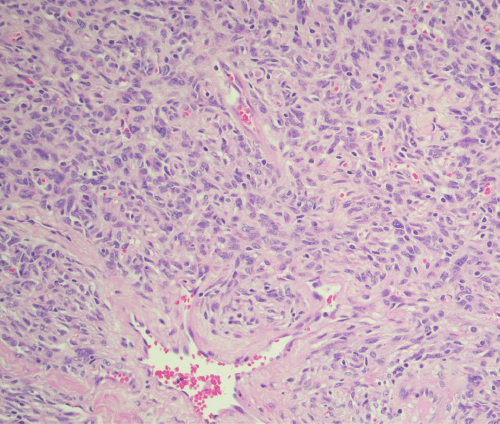

A 65-year-old female presented with a mass in the left parotid gland, which had been present for several years but had recently exhibited an increase in size. She was initially referred to a plastic surgeon for evaluation. Physical examination revealed a firm, mobile mass within the superficial lobe of the left parotid gland. Magnetic resonance imaging (MRI) confirmed the presence of a well-circumscribed, superficial lesion within the left parotid gland, without evidence of invasion into surrounding structures or cervical lymphadenopathy (Figure 1). Following these findings, the patient was referred to a head and neck surgical oncologist for further management.

Figure 1. MRI of Left Parotid Gland Solitary Fibrous Tumor. Published with Permission

(A) Coronal view and (B) Axial view demonstrating a well-circumscribed, avidly enhancing, oval-shaped soft tissue mass, measuring approximately 3.3 × 2.1 cm. The lesion appears to arise from or is immediately adjacent to the superior pole of the superficial lobe of the left parotid gland, without definitive invasion of surrounding structures